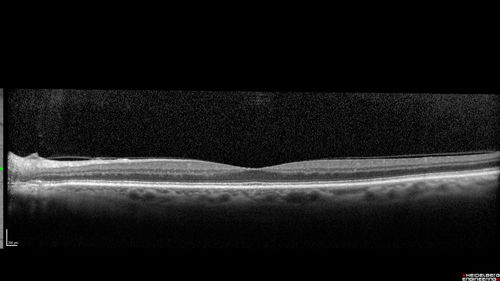

Perifoveal Microaneurysm - Not Diabetic (also reticular pseudodrusen)

87 year old female with fluctuating macular edema in the right eye from a perifoveal MA. (no treatment). VA 20/40 OU